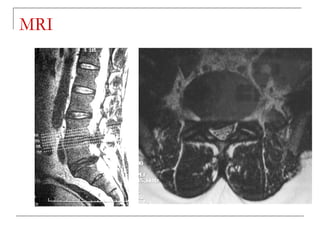

MRI

 -better soft tissue visualization

 -disc

 -ligaments (ALL,PLL)

 -nerves (spinal cord, roots)

 -bone marrow

 -pus collection